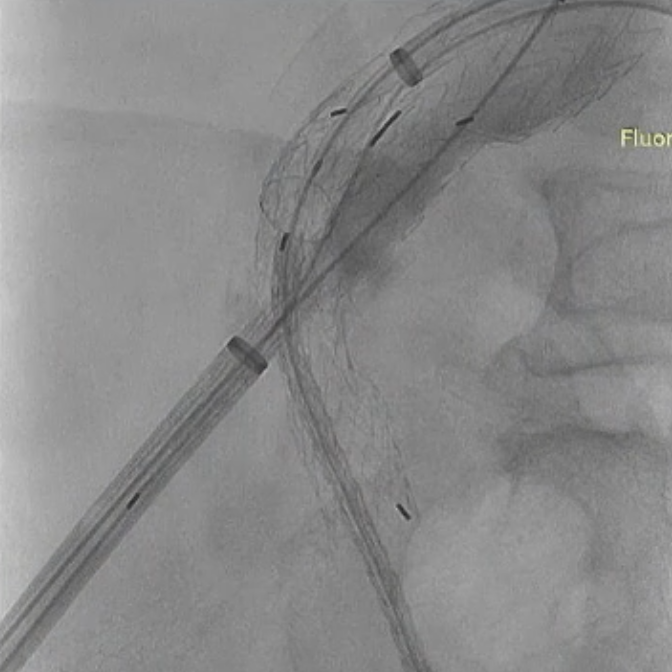

手术过程:根据患者及家属要求保双侧髂内,遂计划双侧髂内重建,右侧优先,左侧髂内情况尝试开通。手术中,先进行造影和翻山建立通路。

造影

翻山建立通路